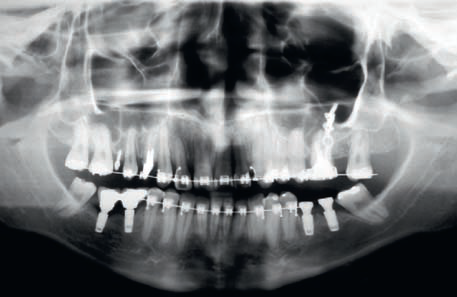

- Pacjentka w wieku 26 lat i 2 miesięcy zgłosiła się na pierwszą konsultację w gabinecie ortodontycznym z główną skargą, że „górne zęby zeszły w dół”.

Streszczenie: Celem niniejszej pracy kazuistycznej jest opis wady dotylnej: II klasy kłowej z protruzją zębów siecznych i z nasiloną ekstruzją zębów w górnym lewym kwadrancie, która uniemożliwiała rehabilitację protetyczną bezzębnych przestrzeni w żuchwie. Znaczącej intruzji ortodontycznej dokonano za pomocą miniimplantów, a następnie minipłytek w połączeniu z aparatem stałym i łańcuszkami elastomerowymi. Dowiedziono, że odpowiedź biologiczna zębów i otaczających struktur kostnych na intruzję okazała się prawidłowa i akceptowalna. Klinicznie intruzję zębów trzonowych lewej połowy szczęki wraz z odzyskaniem przestrzeni na uzupełnienie braków zębowych osiągnięto za pomocą stałego aparatu ortodontycznego powiązanego z TAD. Biomechanika ta umożliwiła również uzyskanie I klasy kłowej, przywróciła stan zdrowia przyzębiu i pozwoliła na rehabilitację protetyczną, co ostatecznie odtworzyło prawidłową okluzję i estetykę oraz zadowalającą funkcję.